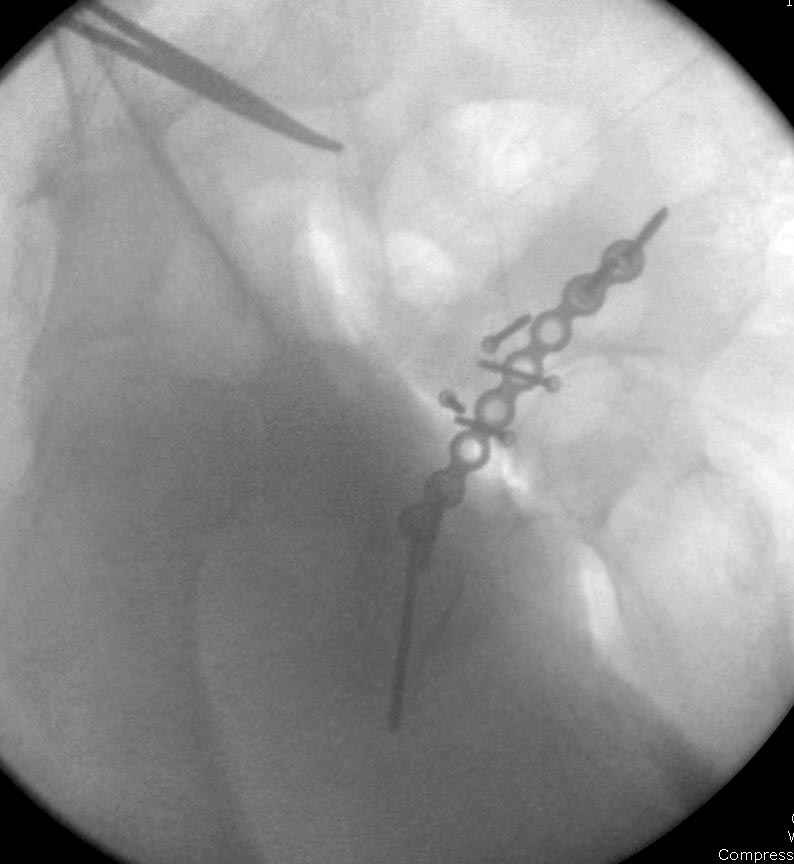

Работаем вместе с хирургами-травматологами (в штатах все травмированные больные поступают, как больные хирургической службы, ортопед выступает в качестве консультанта), т.е. мы даем рекомендации о проведении профилактики тромбоза, совместно решаем о проведении фильтра - вена кава фильтр (см. приложение).

Если вена кава фильтр, хирурги проводят эту процедуру, а медикаментозную профилактику назначаем сами.

Больные с ацетабулярными и тазовыми переломами, идущие на операцию, по протоколу исследуется до операции на состояния сосудистой системы доgплером, который повторяется после операции перед выпиской (были множество случаев позднего развития ДВТ в после операционном периоде)